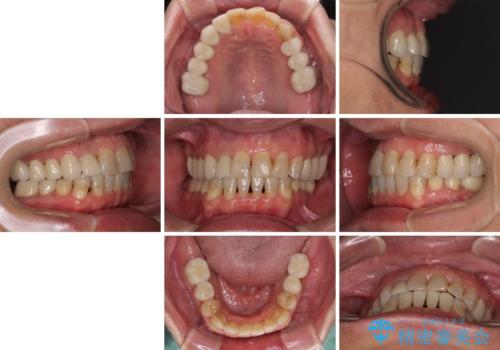

矯正治療を希望して来院されましたが、歯周病を併発していたため、矯正治療開始前の処置が非常に多くなりました。特に歯槽骨の再生治療を行ったため、外科処置後の静置期間が長くなり、4年弱の治療期間となりました。

治療後には咬みやすさだけでなく、前歯が大変審美的に仕上がり、患者様には大変満足していただきました。